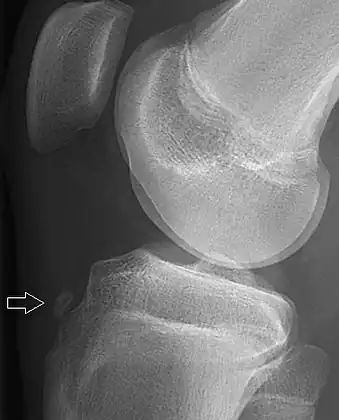

Knee showing tibial tuberosity avulsion fracture (and proximal tibial fracture)

X-ray of a 15-year-old male, showing an older avulsion fracture of the tibial tuberosity.